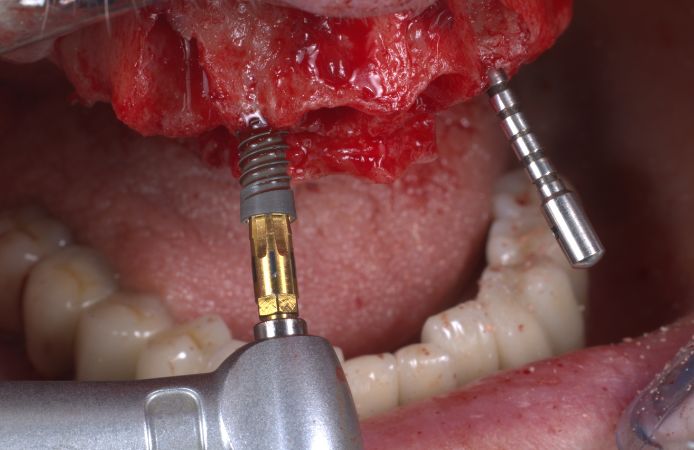

Figure 9.

Placement of four Neoss Multi-Unit Abutments 30° 3.0 mm. The abutments were torqued to 32 Ncm.

Figure 10.

The angulated Neoss Multi-Unit Abutments re-aligned the prosthesis interfaces to achieve a passive fit of the prosthesis.